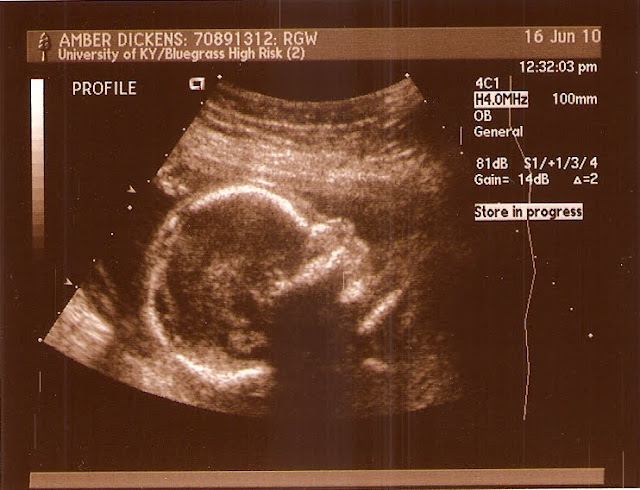

On Wednesday Amber had her 20 week doctor's appointment and gender determination ultrasound (I'm not quite sure if that is the correct terminology, but doesn't it sound cool?). Some friends in the ward watched Greg during the appointment (thank goodness because it lasted almost 4 hours!). Amber's appointment went well and after a lot of waiting we were finally able to see the ultrasound tech and doctor.

I remember Greg's ultrasound and I was so excited to be there for our second child's ultrasound. Amber was pretty sure that the child was a boy and I thought it was a girl (however, with secret hopes it would be a boy so Greg could have a brother). Let's see if you can figure out what our new addition is...

It's a boy! We are so excited. He is currently about 14-15 ounces and is doing great. We should have known it was a boy because on the way over to our friend's house Greg kept saying, "Baby...boy...yeah."

Here are some other ultrasound pictures...